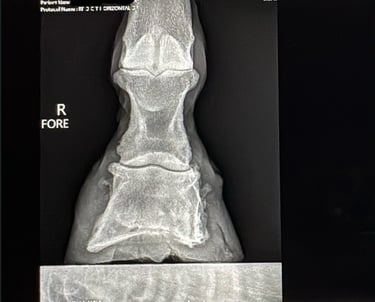

Rennie, a 2016 AQH, is a medical mystery; by all means, he shouldn't be standing, running, or jumping around the paddock. He was rescued in 2023 by a small family who help horses, skin and bones with a severe and constant limp in his right foreleg. We got him in February 2024, a great weight, but he still had a mysterious lameness that we couldn't figure out. After research, I found scoot boots. They took him from constant 3-4/5 lameness to a 1-2 lameness. Sound to be ridden (although he is just a paddock pet) We took x-ray at Texas A&M, the whole team was shocked, wondering how he is still alive with full fusion of his coffin, navicular and P3. His not only walking, but he is sound, happy, and a loving liberty pony. He came from a background of severe abuse. He has the physical and emotional scars of control-based training methods that left deep trauma: rope burns, whip marks, slashed legs, and twisted ears told a story of cruelty I wouldn’t wish on any animal. He had spent his final months before rescue in the auction pipeline.

I turned back to Rennie’s old farrier, the only one he and I trusted, but his flare-ups worsened, and without clear x-rays, we had little understanding of what was truly happening inside his hoof. I consulted my vet about quality of life, corrective shoeing, and every option we had left. When Texas A&M provided new x-rays, the truth was undeniable. His fusion was so severe that most professionals believed there was no choice but euthanasia. One corrective shoer refused to even see him, stating simply, "The horse should be put down."

But the team at Texas A&M saw what I saw—Rennie was defying the odds. Corrective shoeing wasn’t the answer. Traditional shoes would only add more stress, but Scoot Boots gave him freedom. They allowed his hoof to move as naturally as possible, relieving pressure without restricting movement. The specialists were amazed—not just at his ability to move, but at how much the boots had helped him. Without them, he wouldn’t be sound. Without them, I would have had to make the hardest decision.